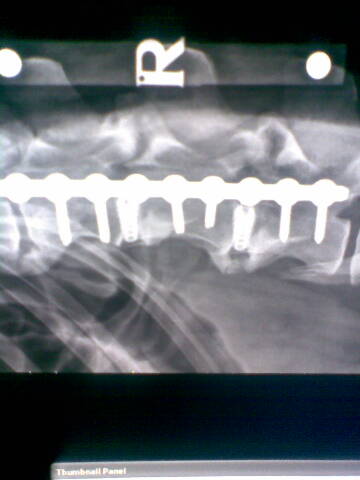

It was make or break. Noel said he could attempt something that had never been done before, the separating of discs from each other and the spinal chord via several screws inserted at a specific angle. These would give the spinal chord the room it needed to recover, or at least give it a better chance, although the procedure was a potentially a highly dangerous one and one that to Noel's knowledge had never been carried out before.

For those of you who are intrigued here's the actual miracle in place. Amazing, amazing people who do these things.

xray1.jpgxray2.jpg